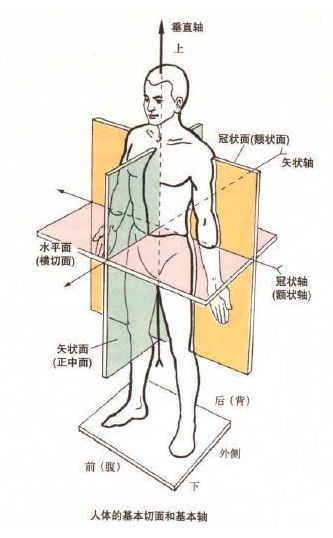

4、体态自我评估方法人的动作可以在三个动作面上进行,即矢状面、冠状面和 水平 面,如下图所示:

观察人的身体有 4 个角度:正面、背面和两个侧面,不同的角度观察的 内容 不同,也因此能发现不同的体态问题。

通过侧面观察,我们能发现自己在矢状面(前后) 的体态问题。正常状态下,人类 的身体中这五个点应该近似位于一条直线的:耳垂、肩峰、股骨大转子、股骨外髁、外踝。

②通过正面观察的体态问题通过正面观察,我们能发现自己在冠状面(左右上下) 的体态问题。

③ 通过背面观察的体态问题